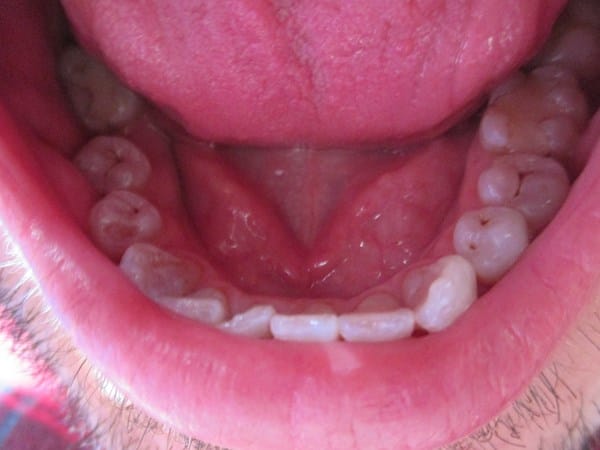

En mi clínica dental un dentista me ha recomendado, a parte de una limpieza, reconstruir (empastar) las piezas 34 y 35, cuando otro dentista me ha dicho que no es necesario la reconstrucción, sobre todo por que me limpio tres veces al día la boca, dentrifico, hilo dental y colutorio de 100% flúor, además no tengo molestias, adjunto fotos para valorar. Una de la parte superior y otro foto de las piezas 34 y 35.